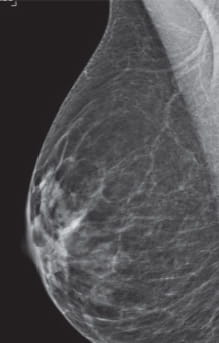

Radiologists classify breast density using a four-level density scale, as determined by a mammogram:

- Category A: Almost entirely fatty

- Category B: Scattered areas of fibroglandular density

- Category C: Heterogeneously dense

- Category D: Extremely dense

Having dense breast tissue may increase your chance of getting breast cancer. Dense breasts also make it more difficult for doctors to spot cancer on mammograms. Dense tissue appears white on a mammogram; lumps, both benign and cancerous, also appear white. So mammograms can be less accurate in women with dense breast tissue.